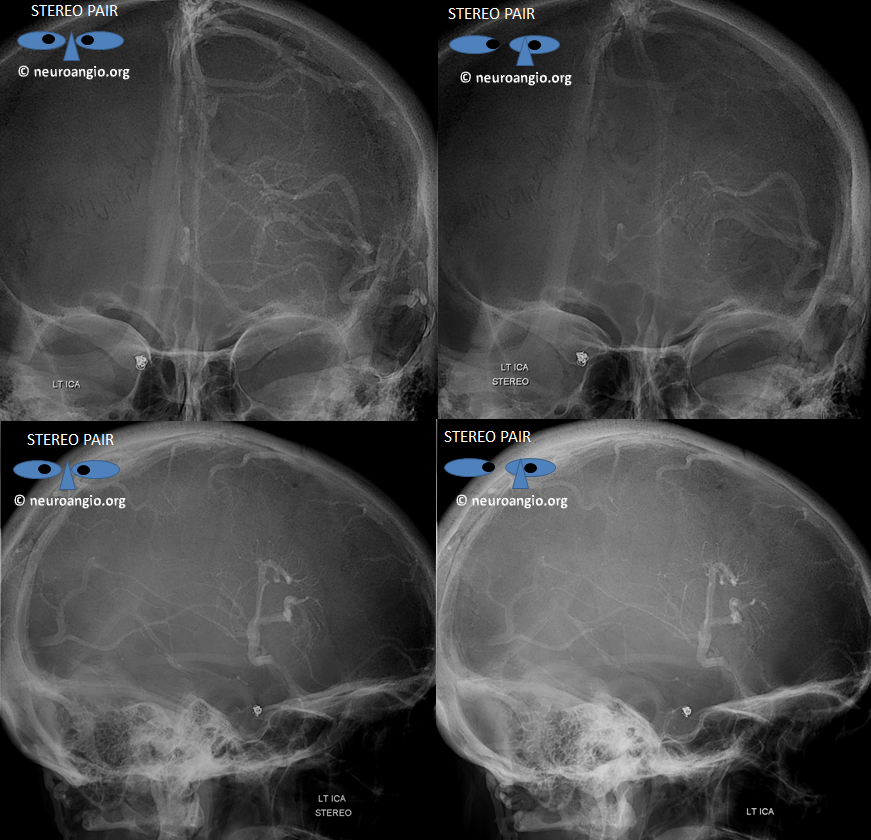

Sagittal Sinus Thrombosis — collaterals.

All of the above anatomic knowledge can become very useful in evaluation of venous thrombosis. Numerous collateral pathways develop in this setting attempting to compensate for the loss. The most dramatic cases usually involve the largest channel — the superior sagittal sinus. In this case, a man presented with what initially was thought to be vasculitis-related brain hemorrhage. Subsequent workup led to an angiogram, where sagittal sinus thrombosis with extensive trans-cerebral and trans-osseous emissary vein collateral channels was seen. In retrospect, these findings were present on the patient’s earlier contrast MRI. “Venovibe” or other contrast-enhanced MR venograms can very sensitive, particularly when interpreted with the appropriate index of suspicion. Noncontrast 2-D time of flight MRV I consider to be next to useless as a problem-solving technique. Any thin-slice postcontrast T1 study is vastly superior.